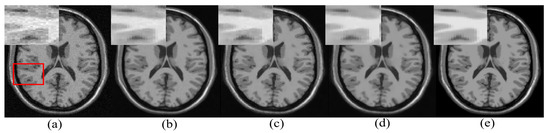

One real MR image is randomly selected, degraded with 2% Gaussian noise, and is denoised using different algorithms. The denoised images are shown in Figure 6. It can be observed that the proposed approach has reduced smearing of image details (in the yellow box), provides efficient denoising in the smooth region, and estimates edges with comparable quality to existing methods in the cyan box in Figure 6.

Figure 6.

Demonstration of image denoising achieved by different denoising algorithms on real MR images with synthetically added 2% Gaussian noise. From left to right—noisy image, optimized blockwise non local means (ONLM) [57], multi-resolution based ONLM (MRONLM) [41], oracle based discrete cosine transform (ODCT), PCA-based denoising over ODCT (PRINLM) [35], variance stabilized transform with blockwise matching and 4D filtering (VST-BM4D) [25], adaptive ONLM (AONLM) [40], the proposed approach, and the original noiseless image.